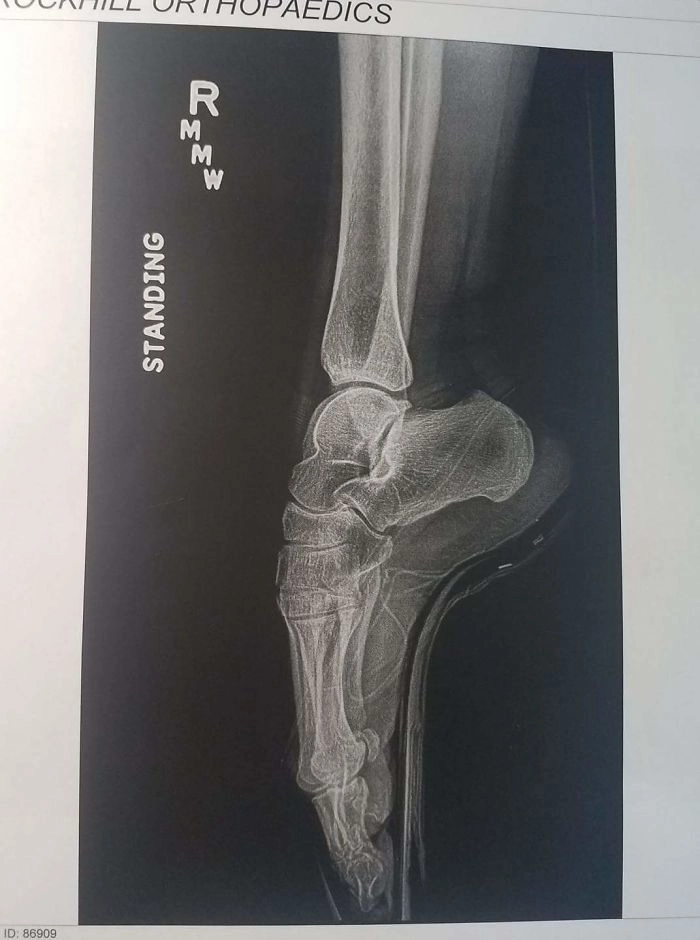

«Рентгеновский снимок моей жены балерины»